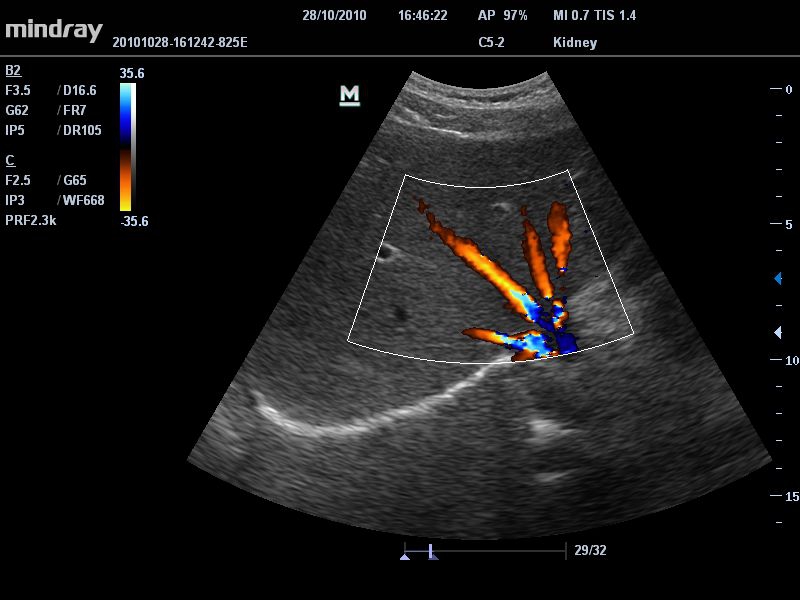

Цветовой допплер:

Да

• Режимы сканирования: B/M/CFM/PDI/Направленный PDI/PW, HPRF, Тканевая гармоника, М- и цветной М-режим.